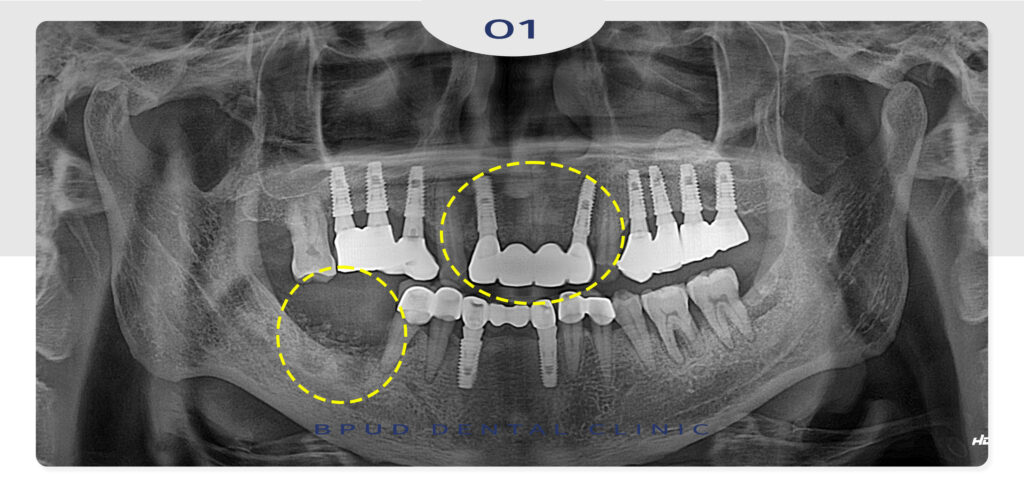

22.11.28

약 3년 뒤, 앞니 보철의 파절과

오른쪽 아래 잇몸이 불편하시다며

오랜 기간이 지나 내원해 주셨습니다.

임플란트 식립 후 오랫동안 관리가 되지 않아

심한 잇몸뼈의 흡수가 일어나 있음을 관찰할 수 있었는데요.

아래쪽의 신경관까지 골흡수가 일어나

재식립이 상당히 어려운 상황이었지만

기존 임플란트를 제거하고 치조골 이식을 통해

다 녹아버린 잇몸뼈를 재건하여 재식립 수술을

진행하기로 계획을 수립하였습니다.